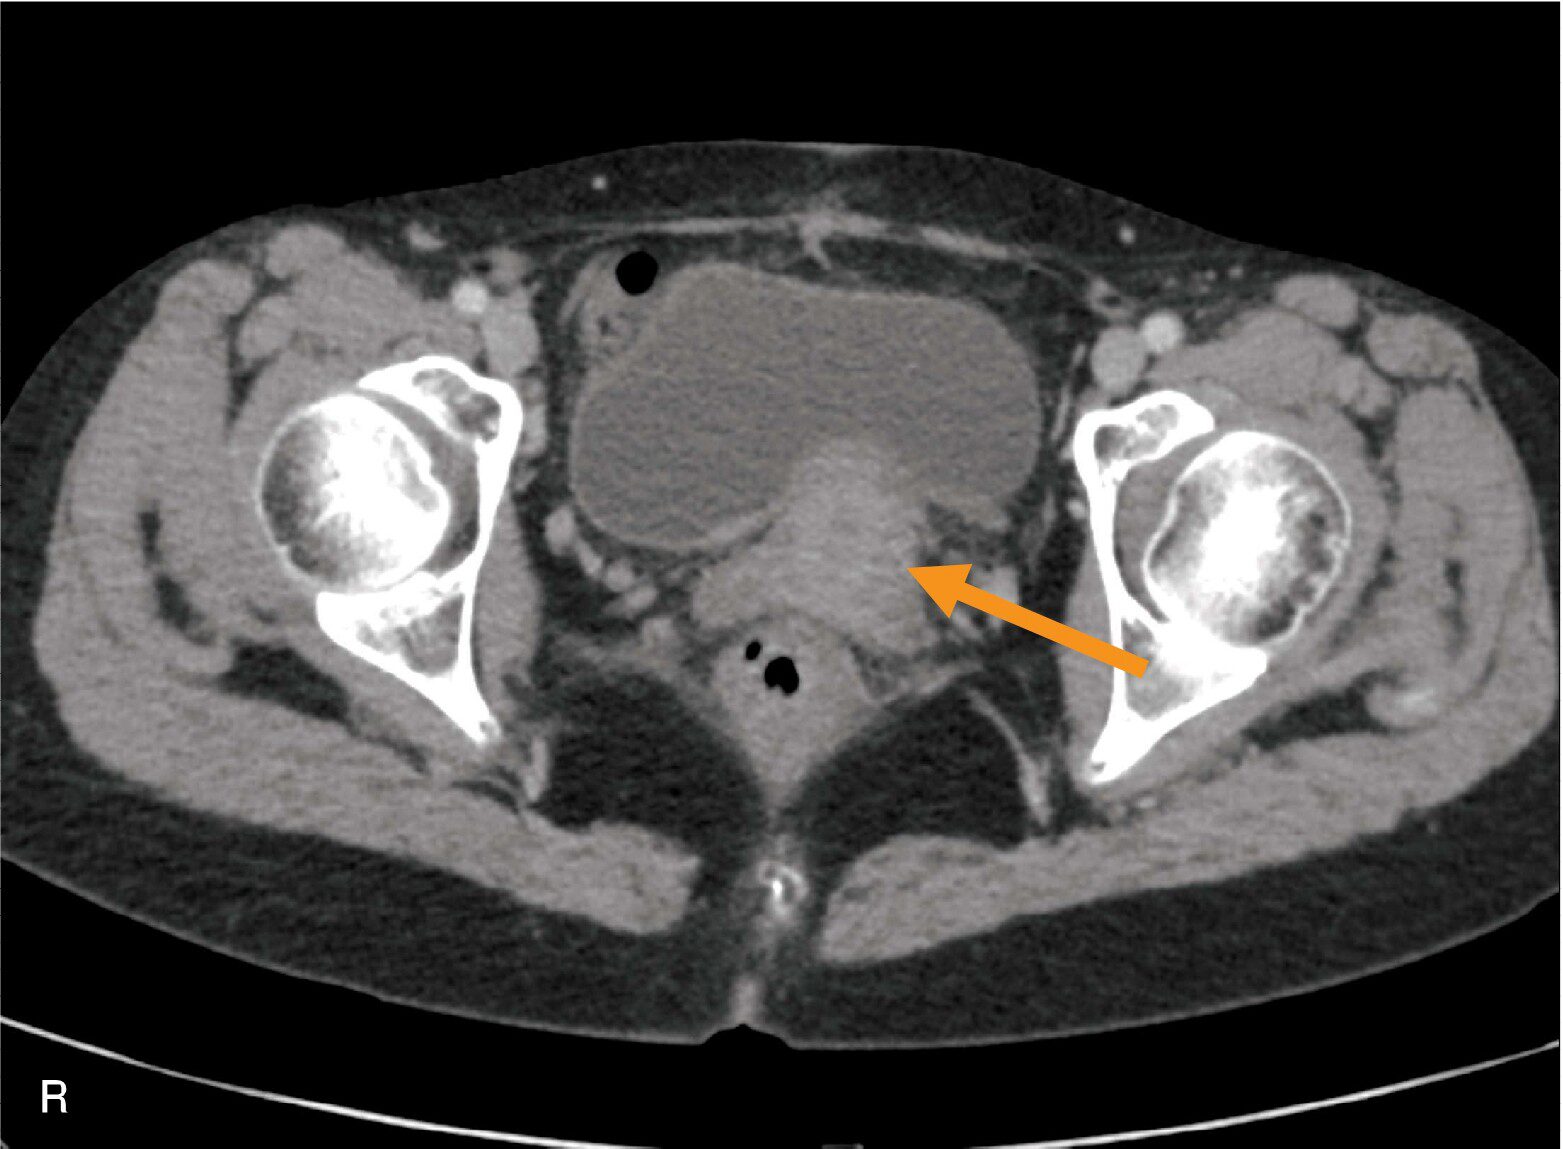

骨盤部のCT像(別冊No.10)を別に示す。矢印で示すのはどれか。